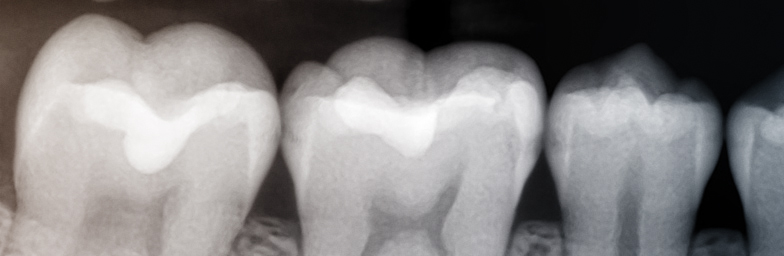

Cu o experiență de peste 20 de ani în domeniul radiologiei stomatologice, cabinetul nostru oferă o gamă largă de servicii de imagistică. Personalul calificat este preocupat întotdeauna să îndeplinească exigențele medicilor colaboratori, dar și să le ofere pacienților o experiență cât mai scurtă și plăcută în cabinetul nostru.

Suntem întotdeauna preocupați de îmbunătățirea calității serviciilor oferite medicilor stomatologi și pacienților noștri, atât prin dotarea cu aparatură de ultimă generație, cât și prin diversificarea tipurilor de examinări și servicii complementare ce se pot efectua în cabinetul nostru.